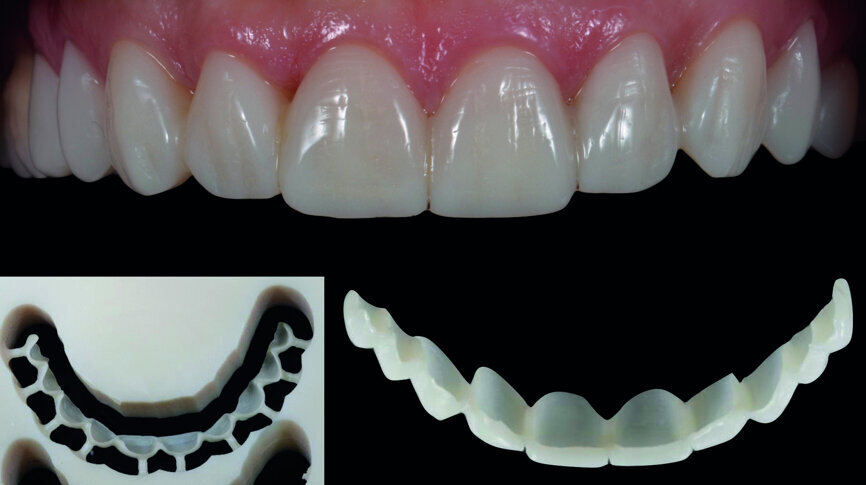

Fig. 14: Digital workflow (3-D printed model, CAD/CAM veneers, adjustments, staining/glazing).

Provisionalisation was executed digitally, using Telio CAD (Ivoclar Vivadent) in the Wieland Select CNC milling machine. The design was performed with the 3Shape DentalDesigner 2015 software (Figs. 12a & b). Two sets of final restorations were fabricated. The set of feldspathic veneers was fabricated on a stone model using IPS Style (Ivoclar Vivadent), while IPS Empress CAD Multi (Ivoclar Vivadent) was used for the digitalset (Figs. 13 & 14). Both sets were examined intraorally with a try-in paste to compare the optical properties of the feldspathic and the CAD/CAM veneers (Figs. 15a–c).